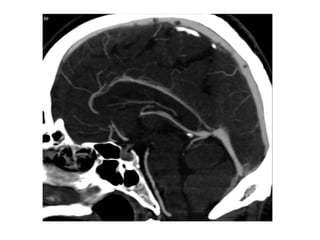

1 superior sagittal sinus

2 inferior sagittal sinus

3 torcular herophili

4 transverse sinus

5 sigmoid sinus

6 jugular bulb

7 internal jugular vein

8 superficial cortical vein

9 vein of Trolard

10 vein of Labbé

11 superficial middle cerebral vein

12 septal vein

13 thalamostriate vein

14 internal cerebral vein

15 great cerebral vein of Galen

16 basal vein of Rosenthal

17 inferior ventricular vein

18 medial atrial vein

20 anterior caudate vein

21 terminal vein

22 direct lateral vein

24 straight sinus

25 sphenoparietal sinus

26 cavernous sinus

28 clival venous plexus

29 superior petrosal sinus

30 inferior petrosal sinus

46 suboccipital veins

47 pterygoid venous plexus

48 true venous angle

51 superior ophthalmic vein

53 sphenopetrosal vein

55 false venous angle

b) Deep Cerebral Veins :

-Consist of paired internal cerebral veins , the

basal vein of Rosenthal & the vein of Galen